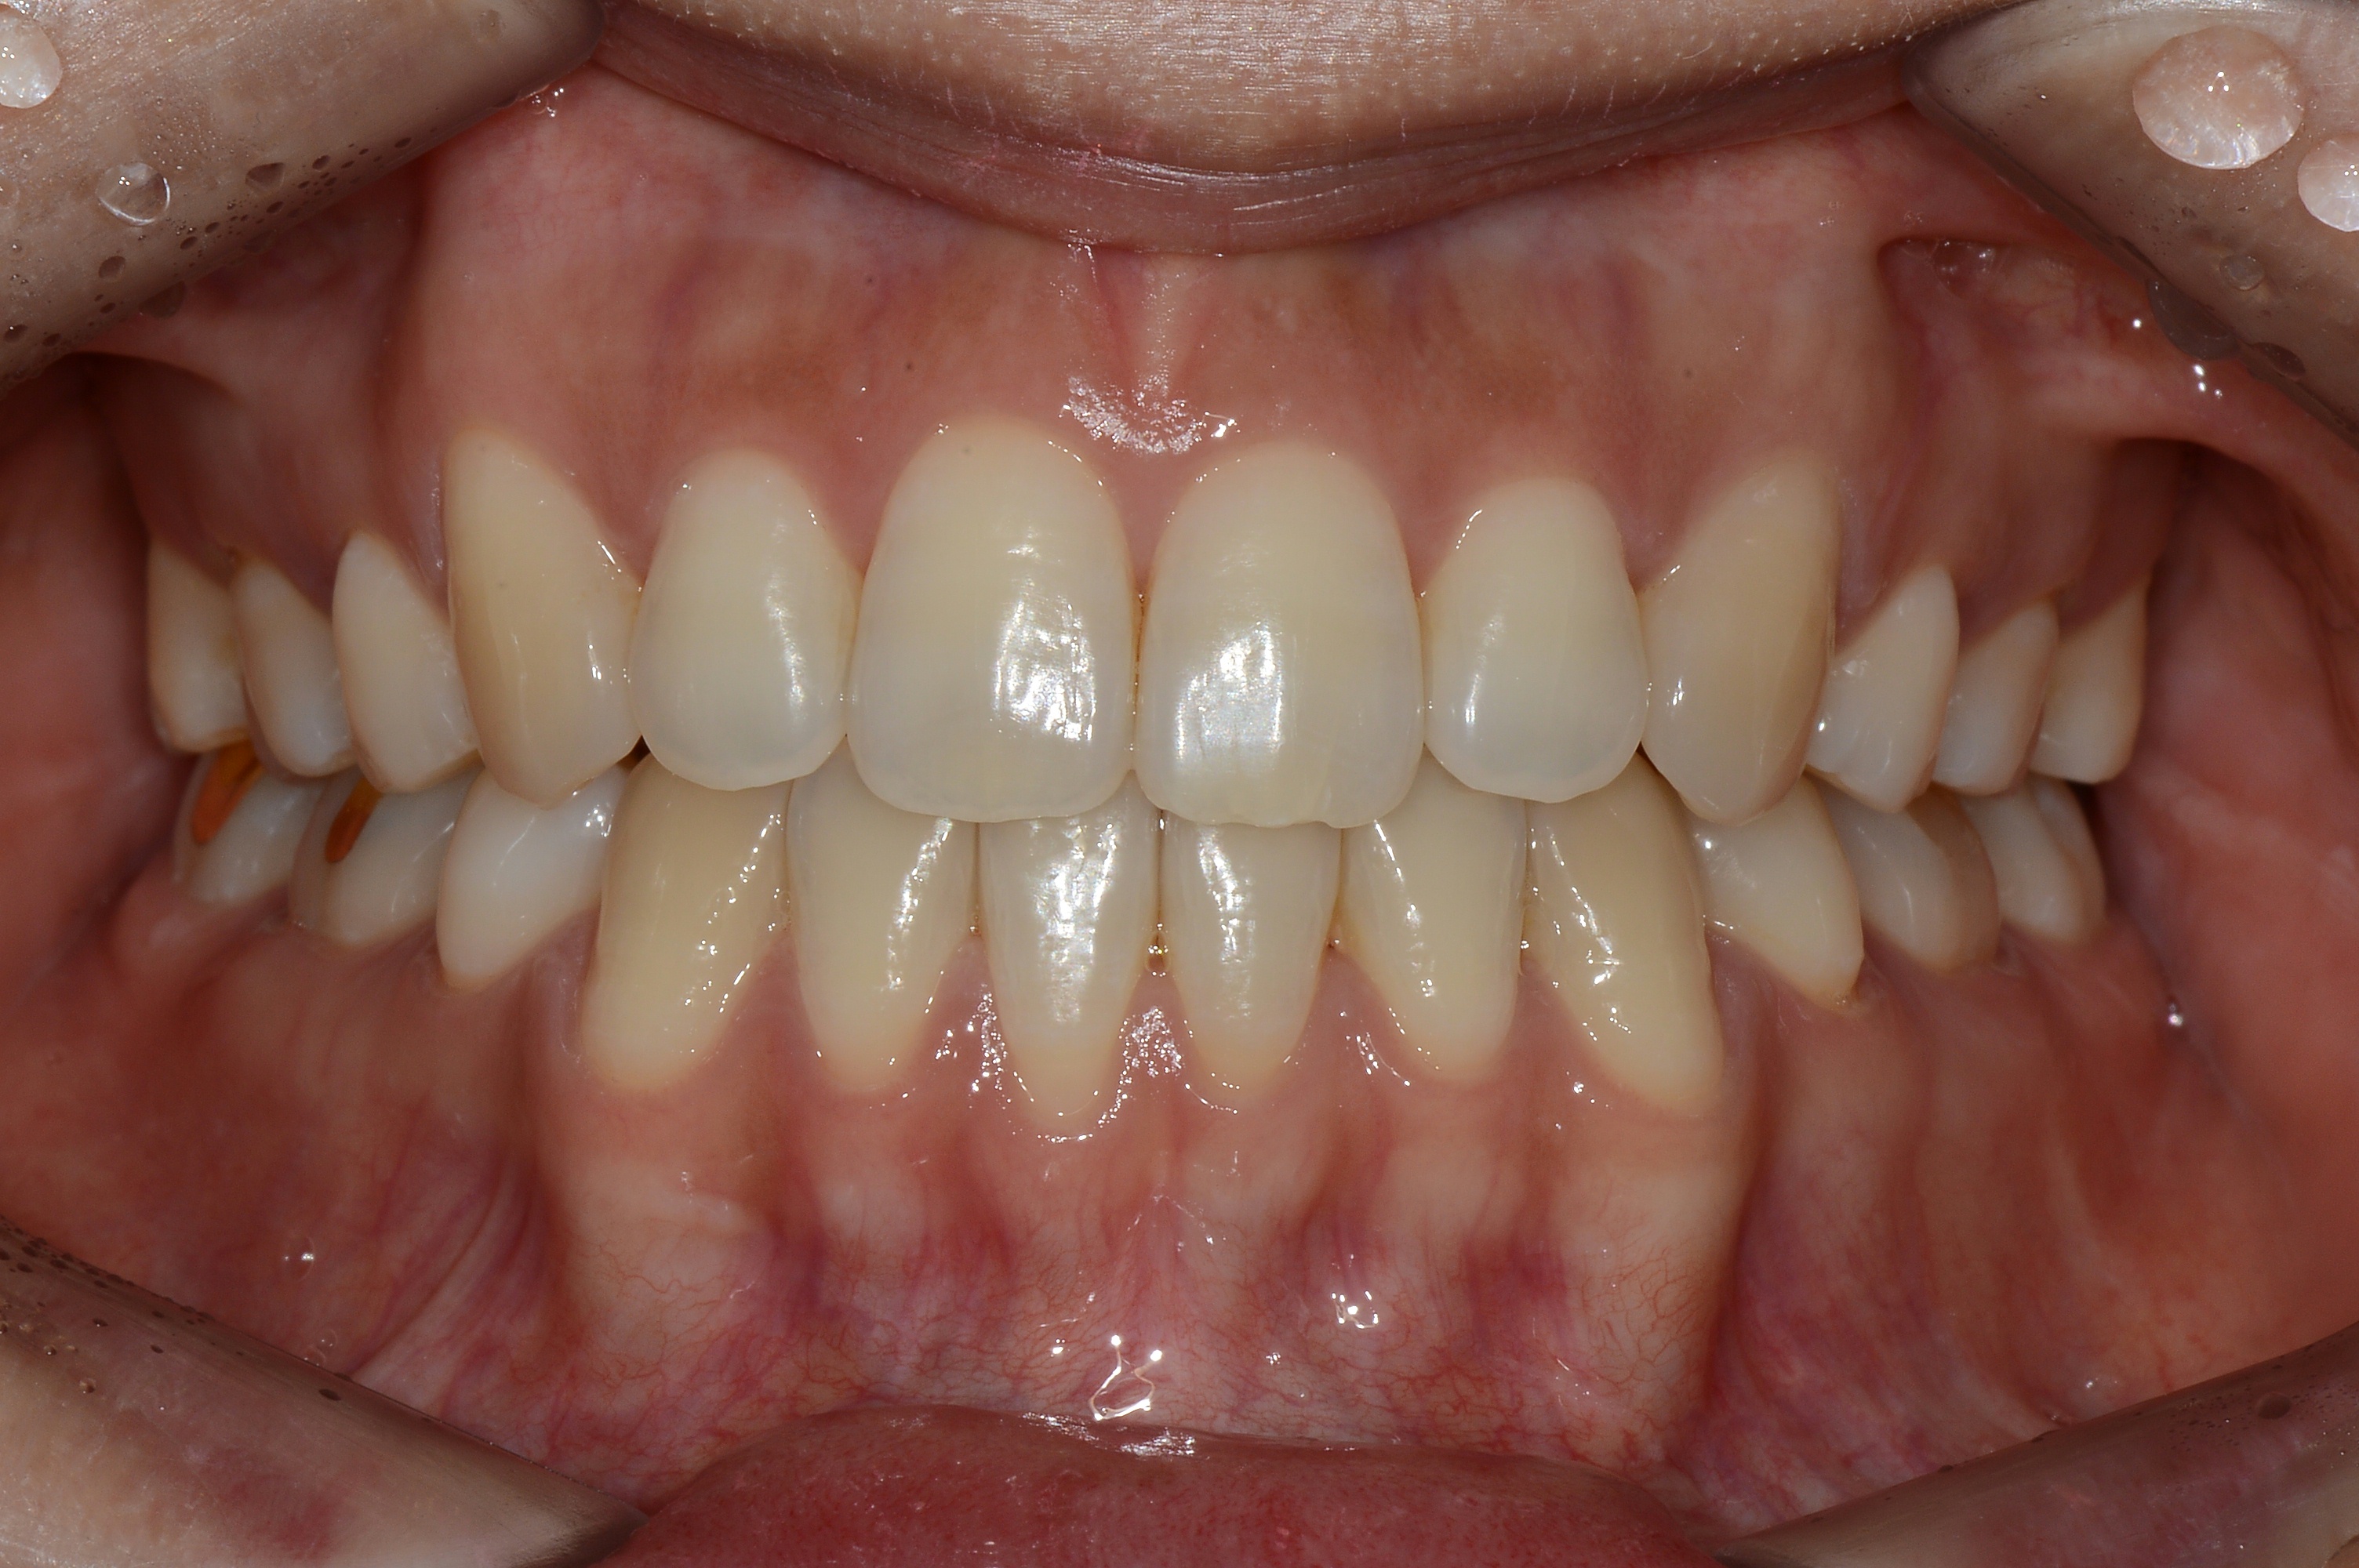

치료 전 사진입니다.